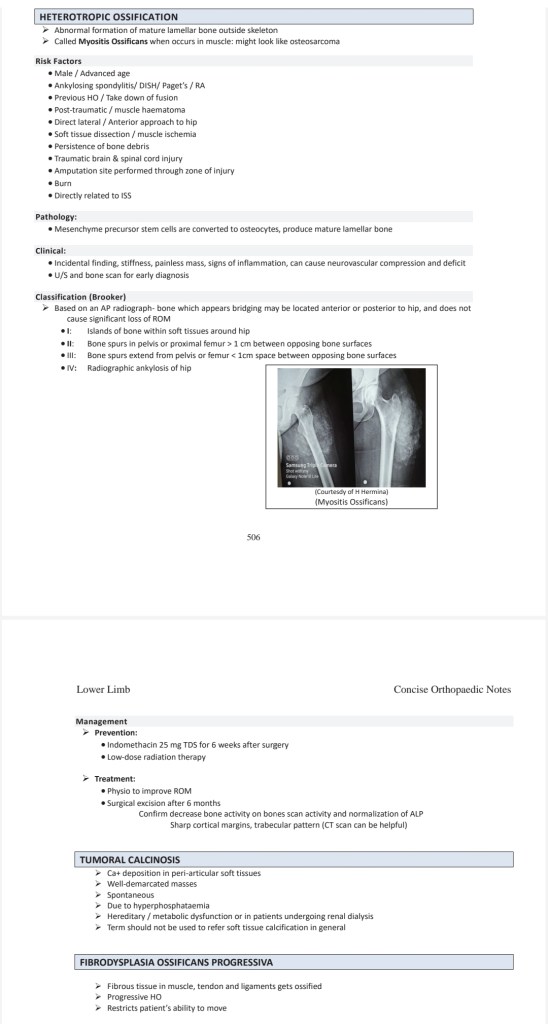

Heterotropic ossification & Myositis ossification